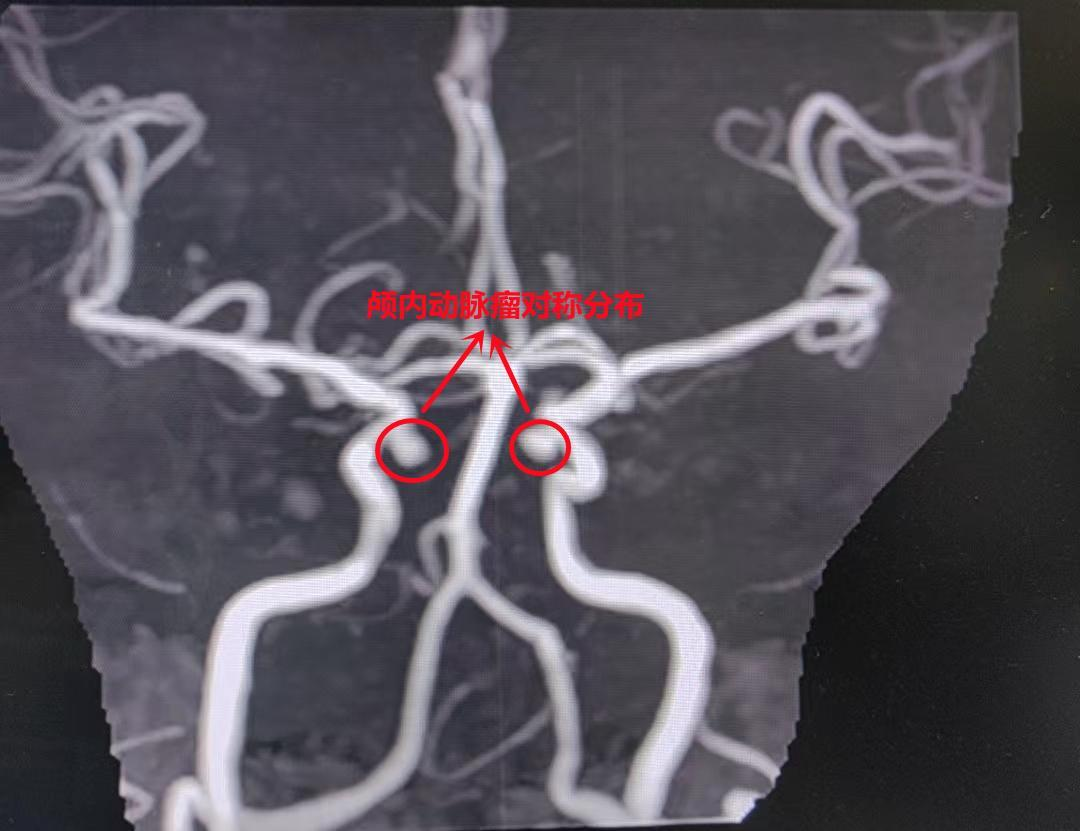

颅内动脉瘤对称分布

核磁共振血管造影(MRA)结果显示,周阿姨双侧颈内动脉虹吸段近眼动脉段对称位置分别有一个小凸起,大小为3.9×3.7mm和3.2×3.5mm。进一步完善脑血管造影(DSA)检查结果提示,左侧动脉瘤形态不规则,呈分叶状,伴有子囊,破裂出血风险极高,需尽快干预治疗。